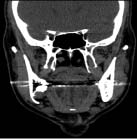

Diagnostic Challenge (continued from page 60)

Diagnostic Challenge (continued from page 60)     In 1942, Edward C. Stafne documented 34 cases of a well-defined radiolucent entity below the inferior alveolar nerve canal, near the mandibular angle.1 The entity is a developmental, lingual cortical bone concavity of the mandible that usually contains salivary gland tissue, fat, muscle, blood vessels, lymphoid tissue … Read more